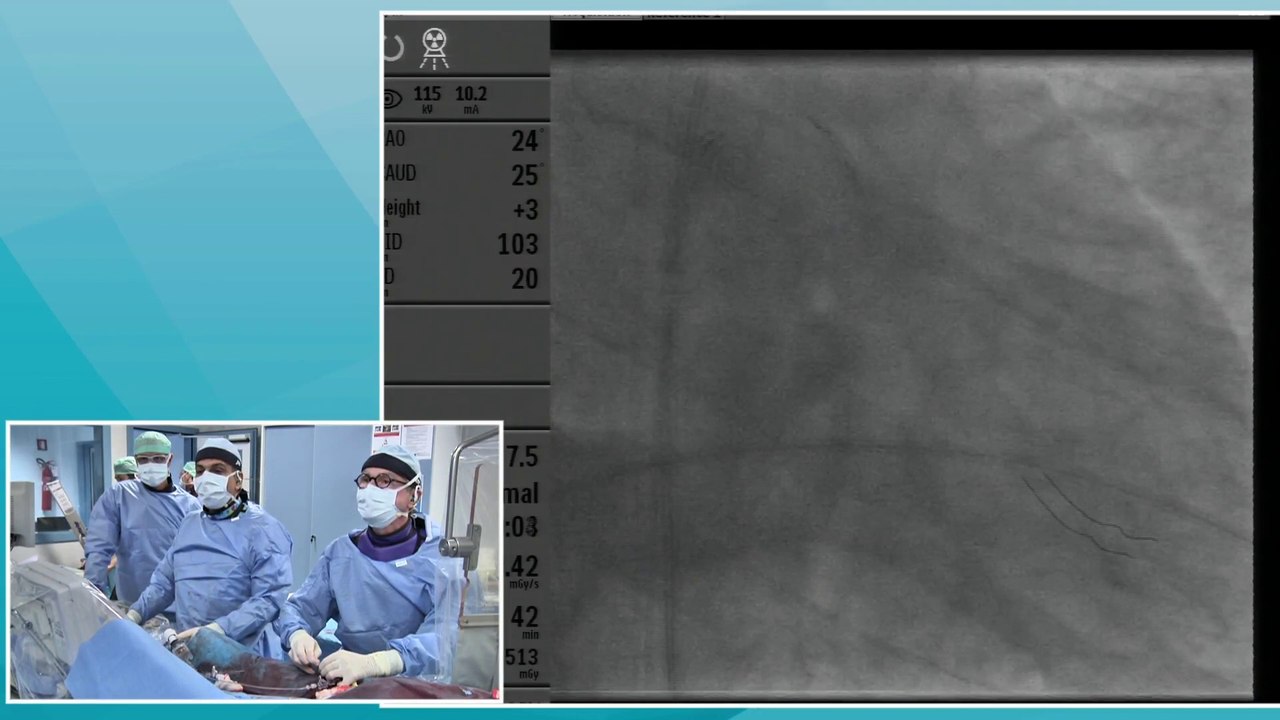

LAD-Diagonal Bifurcation lesion

New Drug-Eluting Technologies

New frontiers of complex SFA angioplasties

Conquering the Complex lesions with step-by-step approach